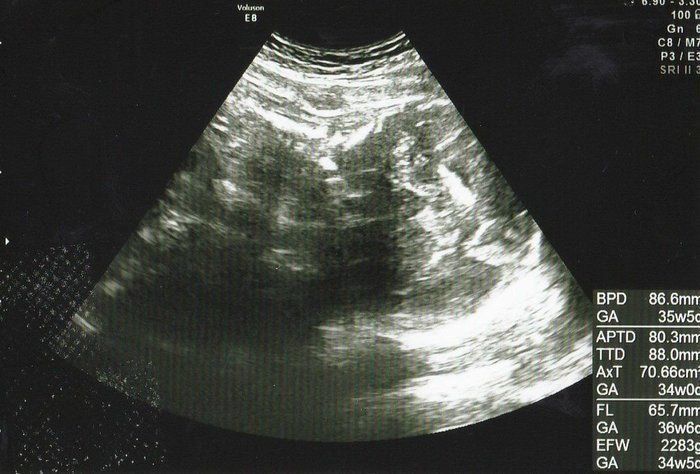

水野谷つむぎさんの妊娠32週目のエコー写真 赤ちゃんの推定体重2080g

宝物の息子とはおなかのなかで対面してた!エコー写真で出会いからこれまでを振り返る

この頃になると股関節痛が酷くなりました。少し歩いただけで、普通には歩けない状態になってしまい、道端でストレッチをしてしのいでいました。